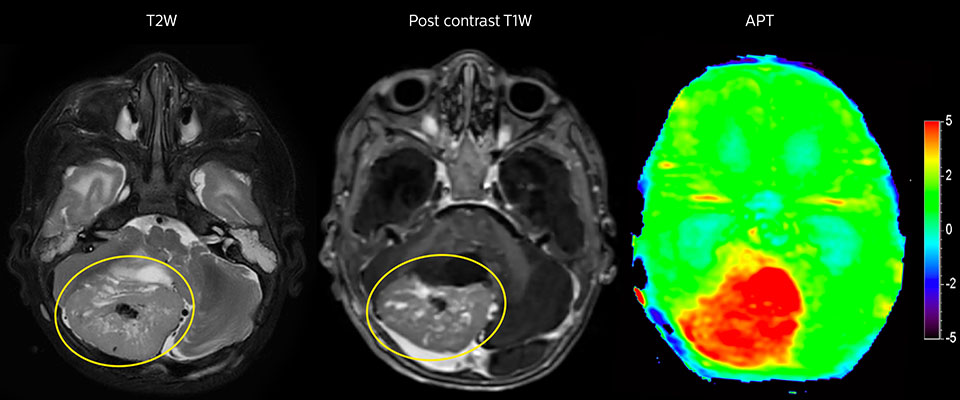

APT imaging of high-grade tumor

Tumor evaluation in a 1-year-old child with medulloblastoma. This aggressive tumor type is very solid and homogeneous. The high APT signal corresponds with the post-contrast image of this high-grade tumor.